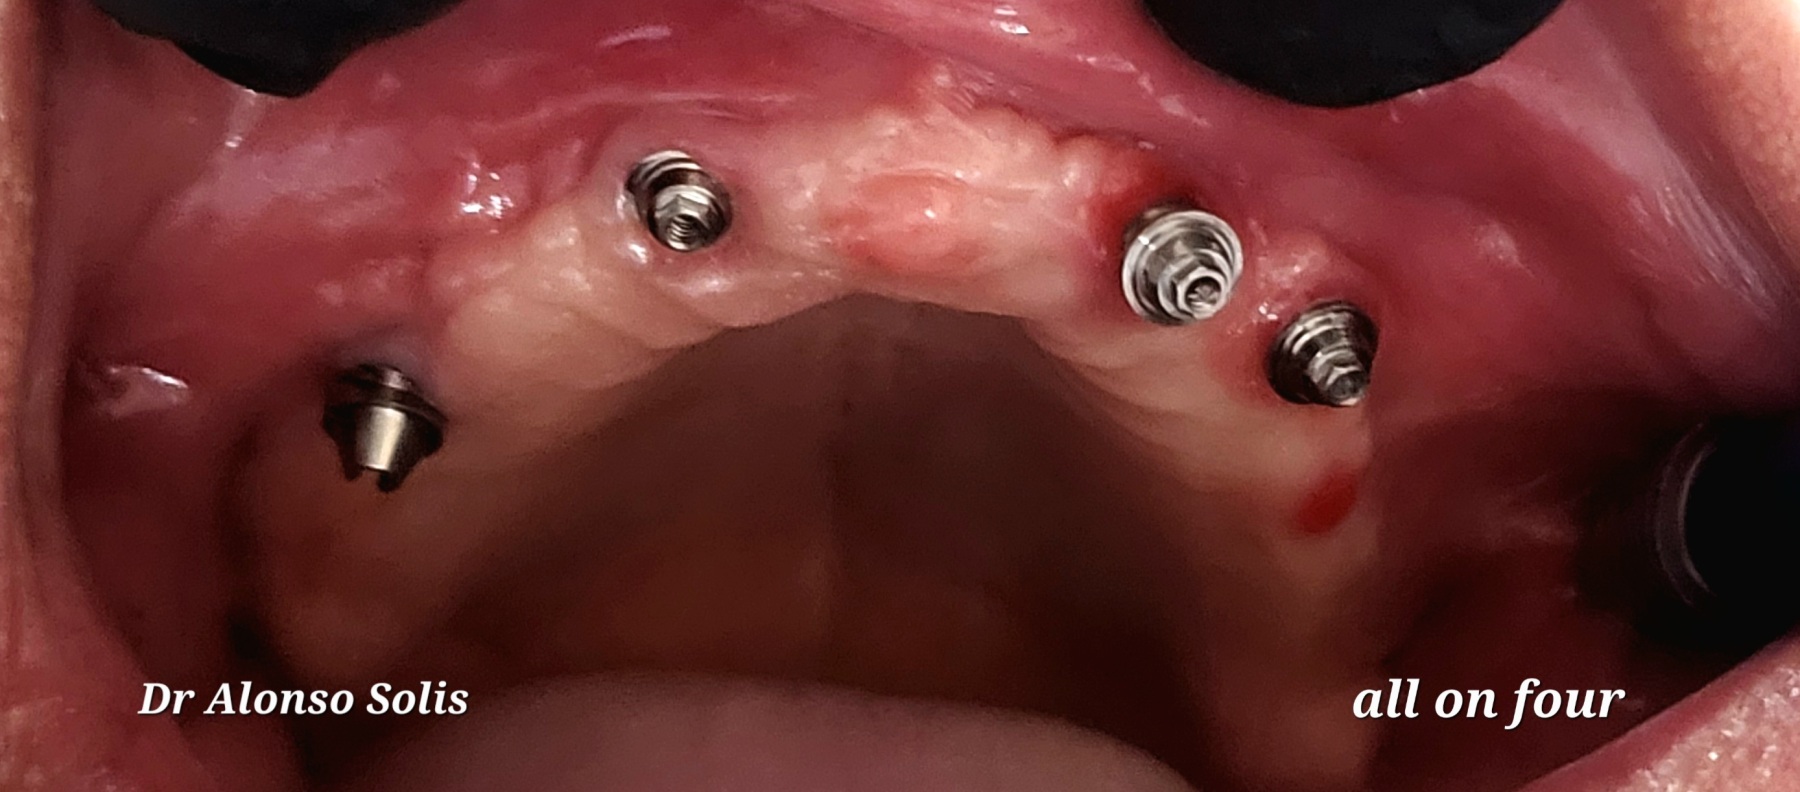

Caso 4

Paciente masculino 65 años, presenta Periodontitis Crónica Generalizada, se realiza extracciones totales de piezas superiores, se colocan 4 implantes dentales para sobredentadura, 4 meses después paciente disfruta de una nueva y renovada sonrisa, sin necesidad de retirársela, ni de preocupaciones de que la prótesis se le desplace al comer o hablar.